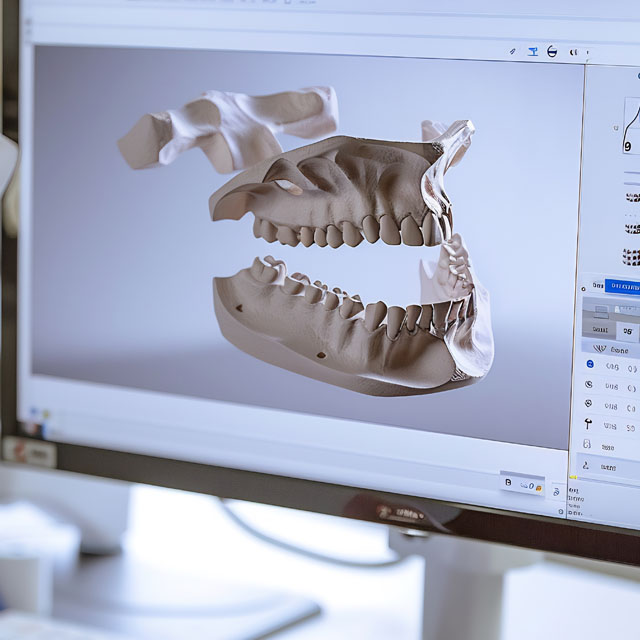

Full Mouth Reconstruction with Implants is a comprehensive solution for patients suffering from extensive tooth loss or severe damage across both arches. This transformative approach restores not only the appearance of your smile, but also the full function and health of your mouth—providing long-term stability, comfort, and aesthetics.

Our personalized approach combines advanced implant techniques—like All-on-4, Single Tooth Implants, and implant-supported bridges—with other restorative procedures tailored to your needs. This may include correcting bite alignment, restoring chewing function, enhancing facial aesthetics, and supporting bone health through grafting when necessary.